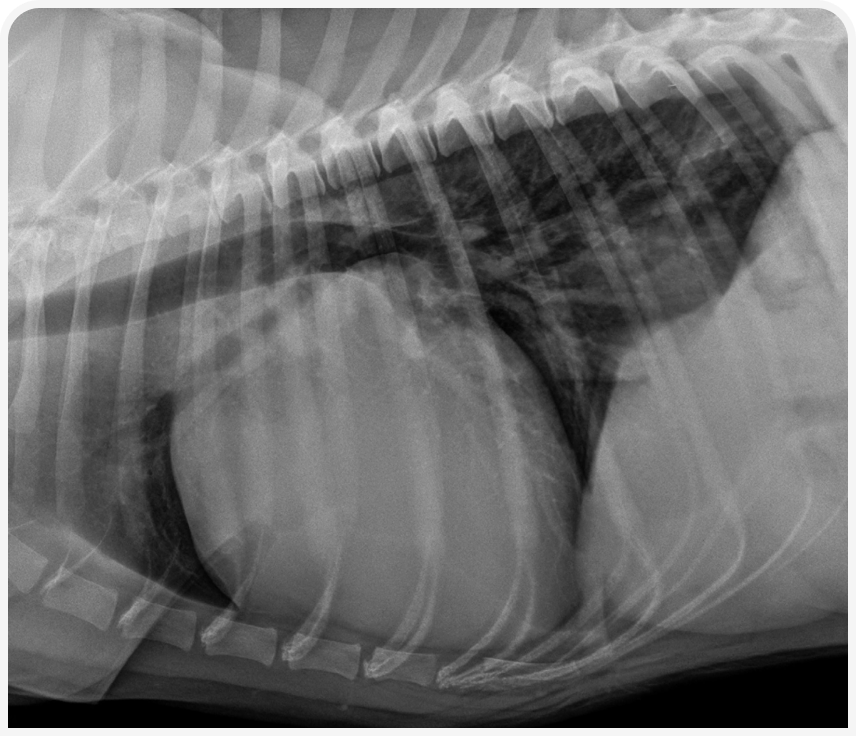

На ранних стадиях заболевания рентгенографические изменения могут быть не информативны. В зависимости от стадии заболевания, рентгенограммы органов грудной клетки могут быть в пределах нормы или указывать на увеличение предсердий и желудочков (обычно левого) с расширением или без расширения тени легочных вен и признаков отека легких (Рисунок 4). В некоторых случаях могут увеличиваться оба предсердия и желудочка. Эхокардиография важна не только как метод выбора для диагностики ДКМП у собак, но и для выявления скрыто протекающего заболевания. При явном заболевании следует исключать расширение левого (а иногда и правого) предсердия и желудочка и снижение систолической функции.